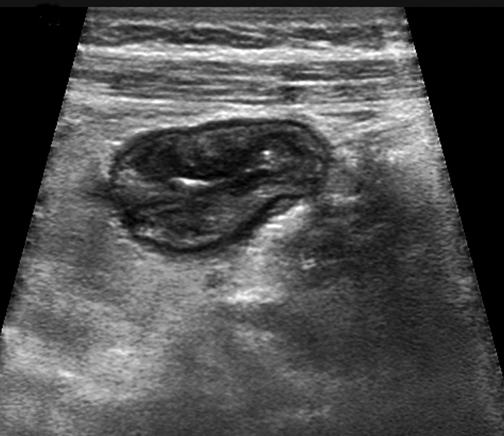

Cross sectional image of the terminal ileum show thickend boLongitudinal image of the terminal ileum show thickend bowel wall and

Cross sectional and longitudinal images of the terminal ileum show thickend bowel wall and inflammatory echogenic fat in a patient with acute CD of the terminal ileum.